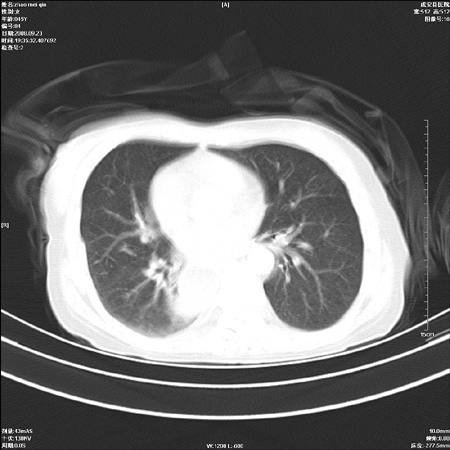

标题: CT15861:女 60 外伤后1小时 胸疼 [打印本页]

标题: CT15861:女 60 外伤后1小时 胸疼

外伤后1小时 胸疼 是外伤后引起的吗?

食道扩张明显下端逐渐变窄,倒像贲门失迟缓

食道ca术后胸腔胃,右肺挫伤?

非外伤性改变,典型的贲门失迟缓症

食道扩张明显下端逐渐变窄,大量食物存留,象贲门失迟缓症。